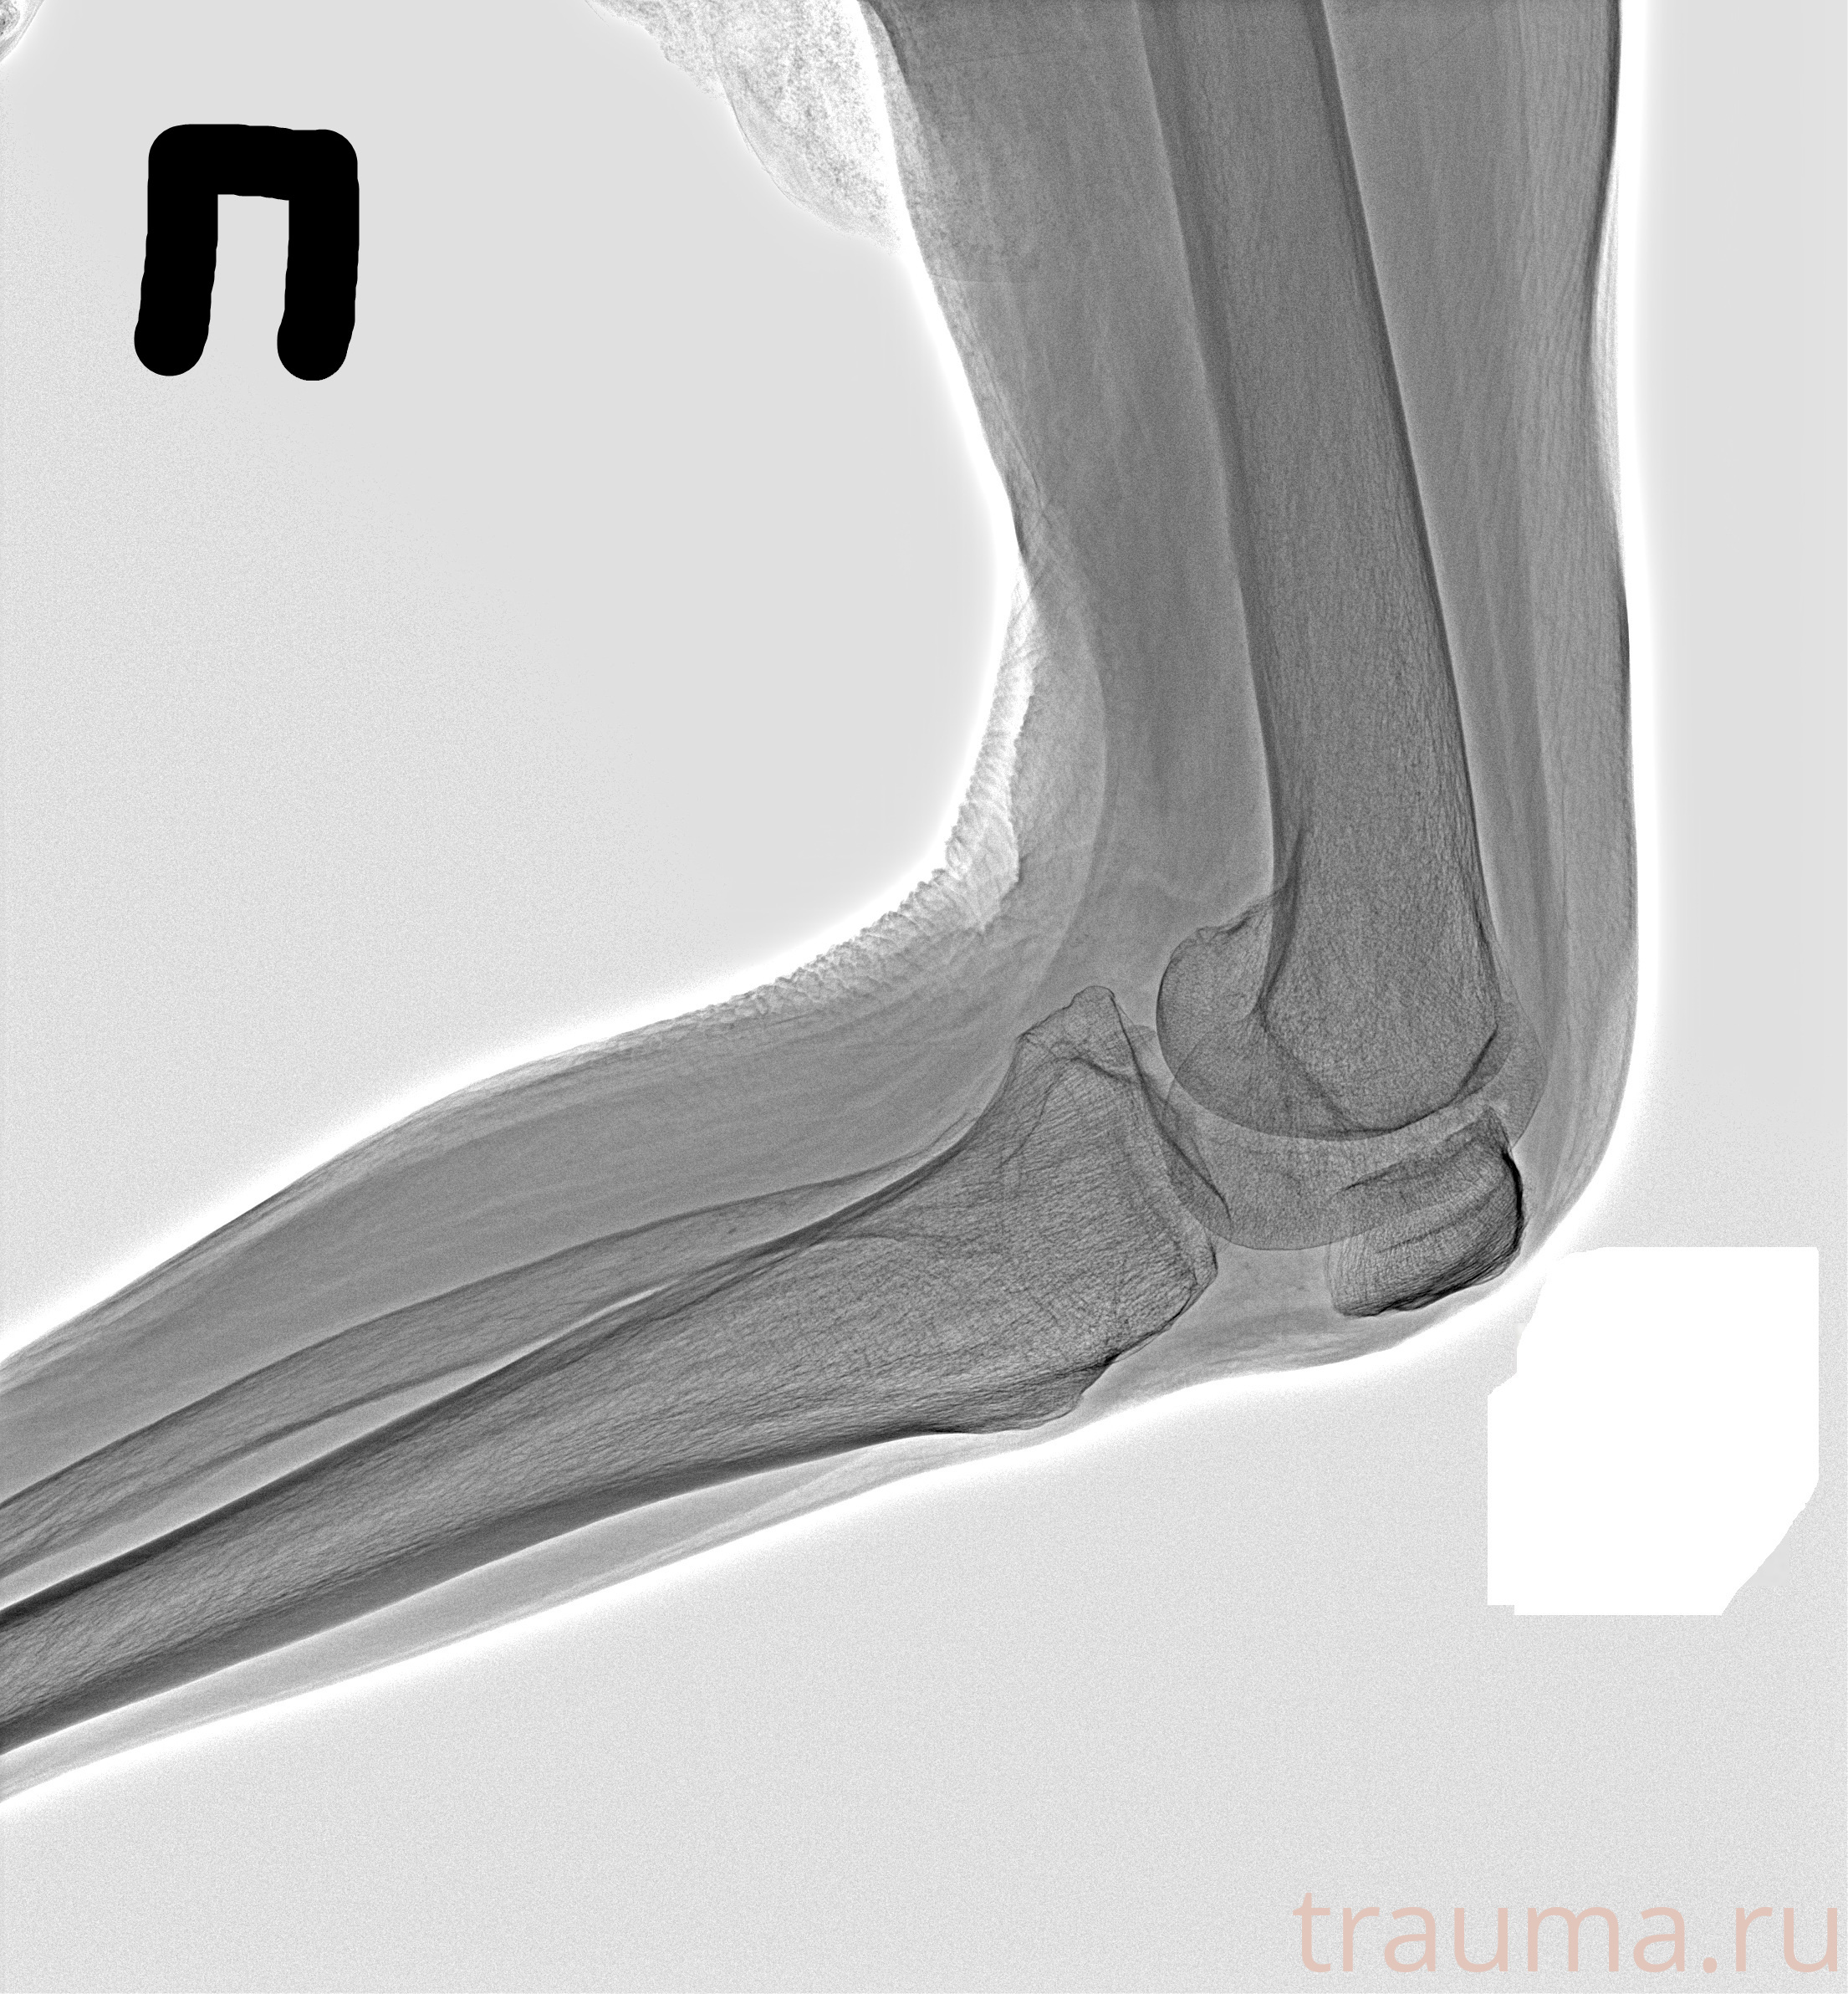

Рентгенограммы

Рентген на дому: по вашему адресу приезжает врач-рентгенолог, травматолог-ортопед с мобильным рентгеновским аппаратом, проводит диагностику травмы или заболевания, делает необходимые рентгенограммы, дает рекомендации по дальнейшему лечению. Получить качественные снимки в домашних условиях возможно благодаря уникальной методике, разработанной МосРентген Центром для института  Склифосовского